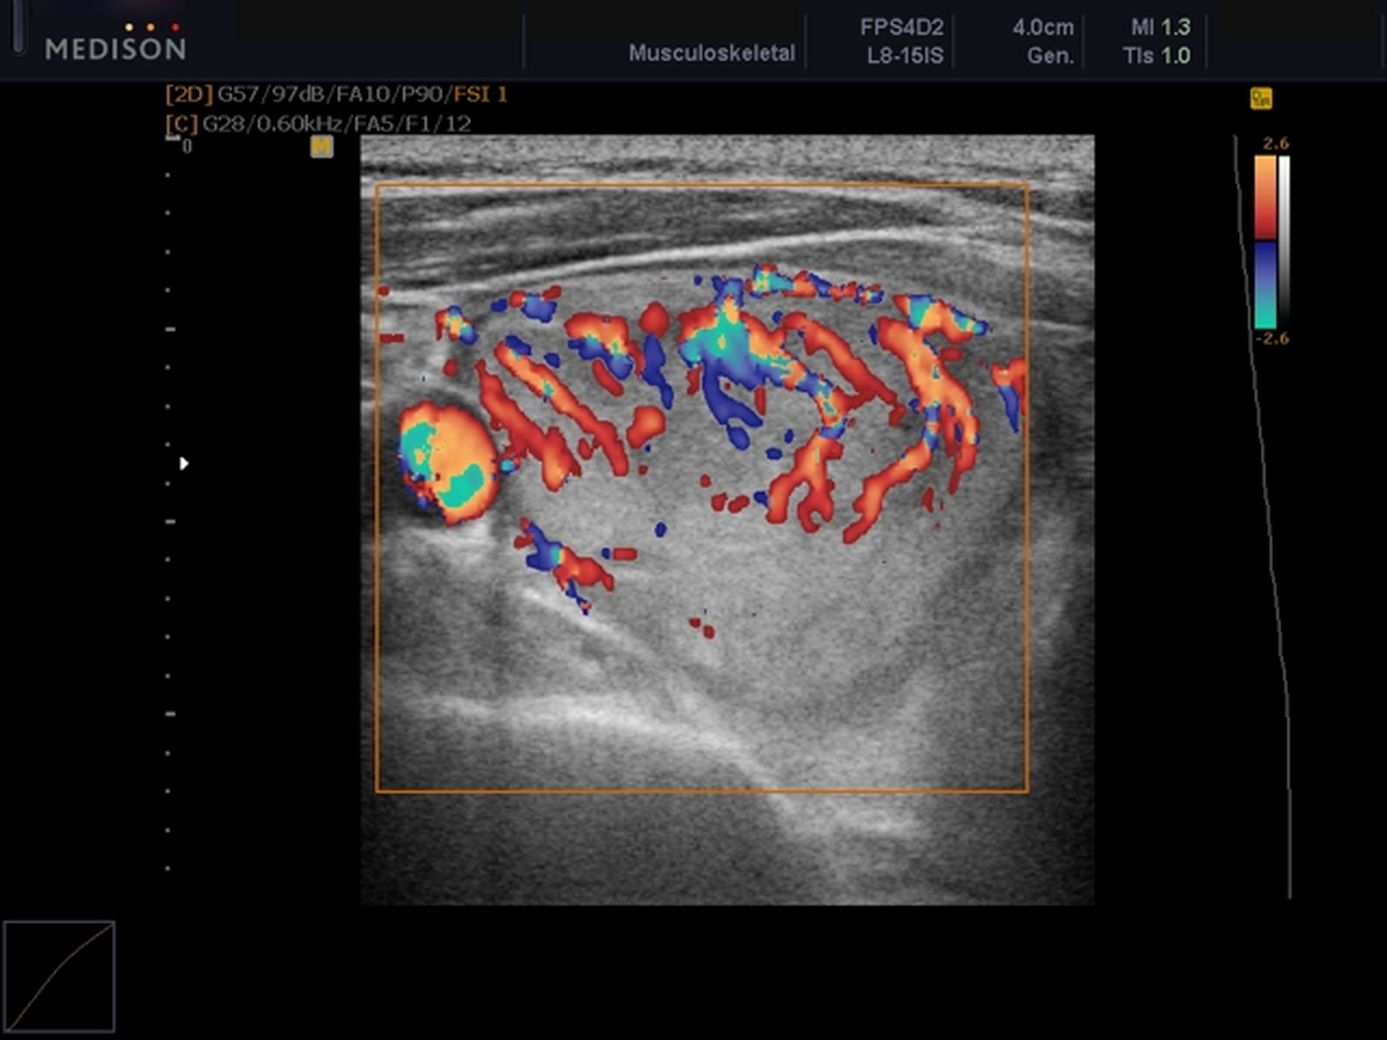

Цдк в узи щитовидной

Цдк в узи щитовидной 110 фото